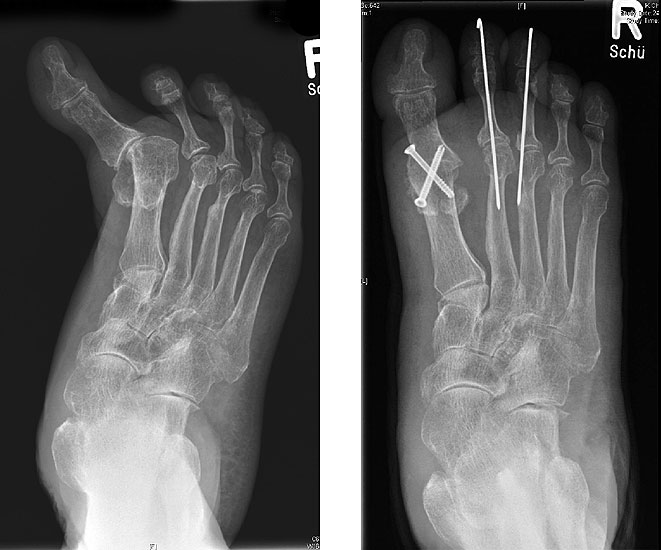

Gute Ergebnisse werden in diesem Fall durch die Arthrodese des MTP-1-Gelenkes erzielt. Bei älteren Patienten kann zum Erhalt der Beweglichkeit eine Keller-Brandes-Prozedur sinnvoll 2327, (Wirth, 2002)

Arthrodese MTP I und weichteilige Rezentrierung MTP II und III (eigenes Bildmaterial)

Abbildung 18

Eine alleinige Implantation einer Prothese oder eines Spacers im MTP-Gelenk bringt bei fehlender Ausrichtung der Zugrichtung der Muskulatur des 1. Strahles keine befriedigenden Ergebnisse.